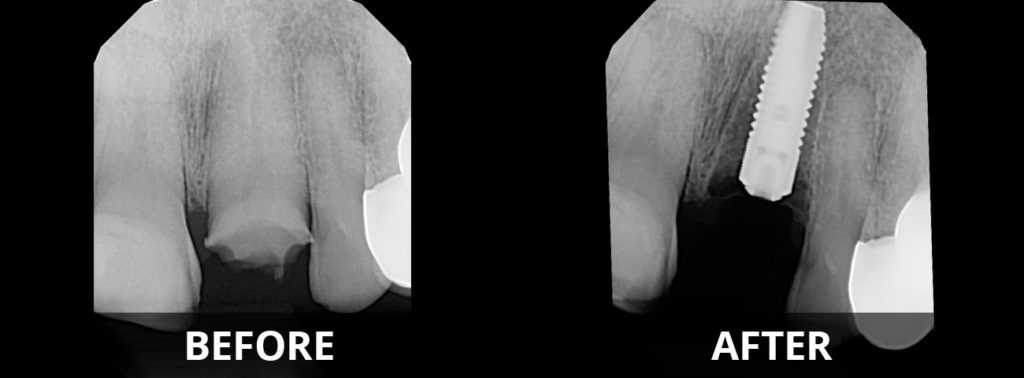

Before and After View

Gallery of Implants

Implant Image Process